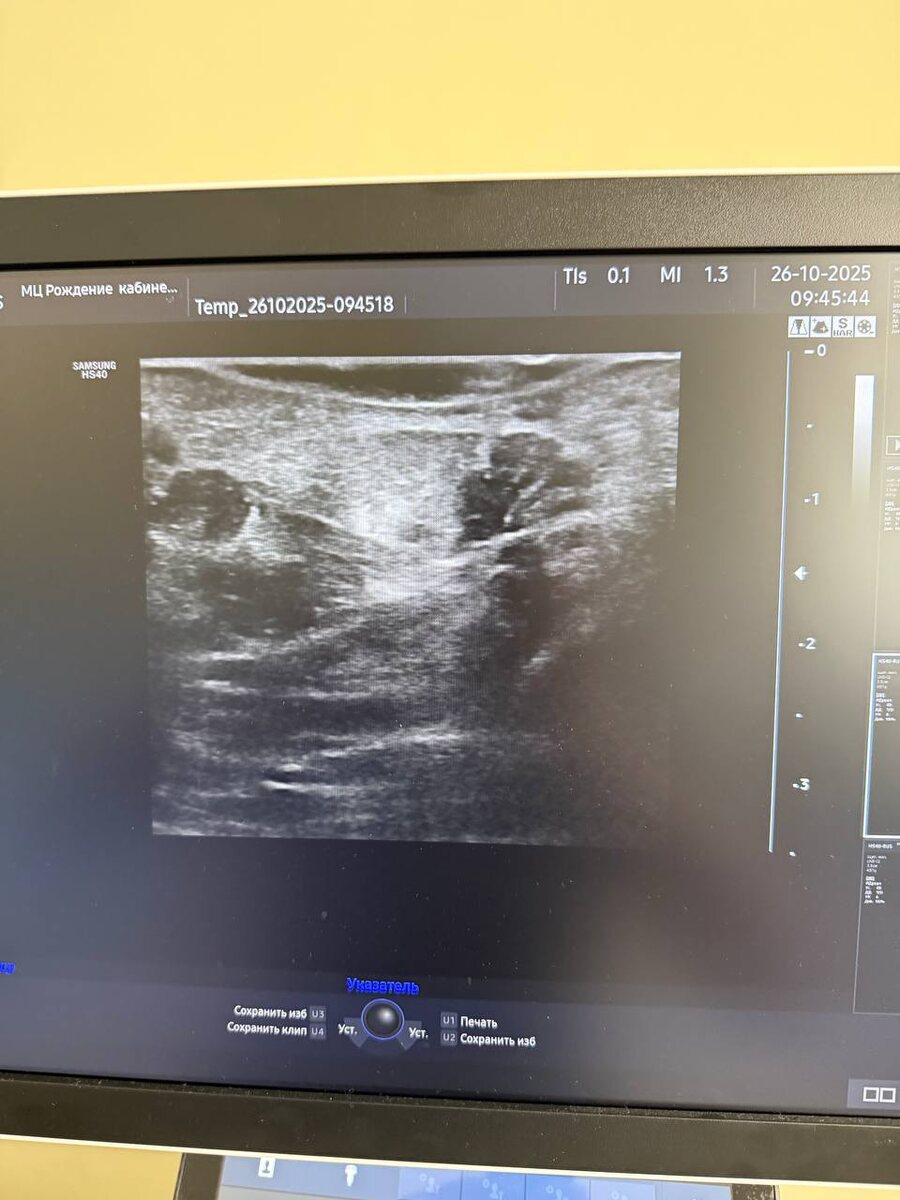

Занимались контрактурой Дюпюитрена, малоинвазивная чрезкожная фасциотомия

Занимались контрактурой Дюпюитрена, малоинвазивная чрезкожная фасциотомия.